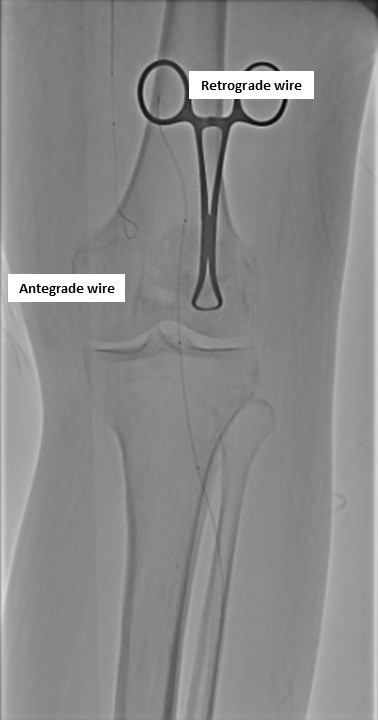

Antegrade puncture was performed, and a microcatheter with a Command 14 guidewire (Abbott Vascular, Santa Clara, CA, USA) was advanced toward the distal SFA but failed to cross because the proximal cap was misidentified due to its blunt and ambiguous appearance. The wire entered aside branch that ran parallel to the true SFA–popliteal course. Given the long chronic total occlusion (CTO) segment and uncertain vessel path, a retrograde approach was pursued to overcome this anatomical ambiguity. Distal ATA access was gained and a CXI Support Catheter (Cook Medical, Bloomington, IN, USA) with a V-18 Guidewire (Boston Scientific, Marlborough, MA, USA) was advanced retrogradely into the popliteal artery but failed to meet the antegrade wire. Another retrograde access from popliteal artery followed a consistent tract. Further attempt from the ATA successfully approached the proximal cap. A 4.0 ¡¿80 mm balloon was advanced retrogradely and inflated at 10 atm. From the antegrade route, the BeBack Crossing Catheter (Bentley InnoMed, Hechingen, Germany) was aimed toward the inflated balloon and successfully punctured the proximal cap, entering the balloon and confirming re-entry. Lesion preparation was completed antegradely, followed by drug-eluting stent deployment in the SFA, drug-coated balloon angioplasty of the popliteal–proximal ATA segment, and plain old balloon angioplasty of the distal ATA to DPA. Final angiography demonstrated excellent in-line flow to the plantar arch.